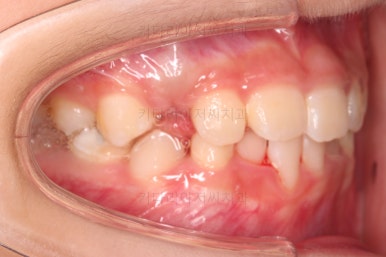

CASE 2.

나이 : 8세

총 치료기간 : 2주(2달 아님, 2주 맞음)

마찬가지로 얼굴모습 부터 분석해요.

골격에 문제가 있는 진짜 주걱턱은 아니라고 판단이 되었어요.

대신 앞니가 거꾸로 물려있어 웃는 모습부터 드러나는 치열의 모습까지 부자연스러운 모습인데요.

이번 환자분도 치료가 굉장히 빨리 끝났어요.

2주만에 해결!

장치도 굉장히 심플하고, 비용도 매우매우 저렴하답니다.

같은 문제를 고급 장치를 이용해서 비싸게 치료할 수도 있지만 목표치가 적당하다면 매우 좋은 치료라고 생각합니다.